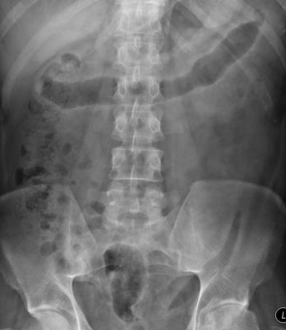

What is this abdominal x-ray showing?